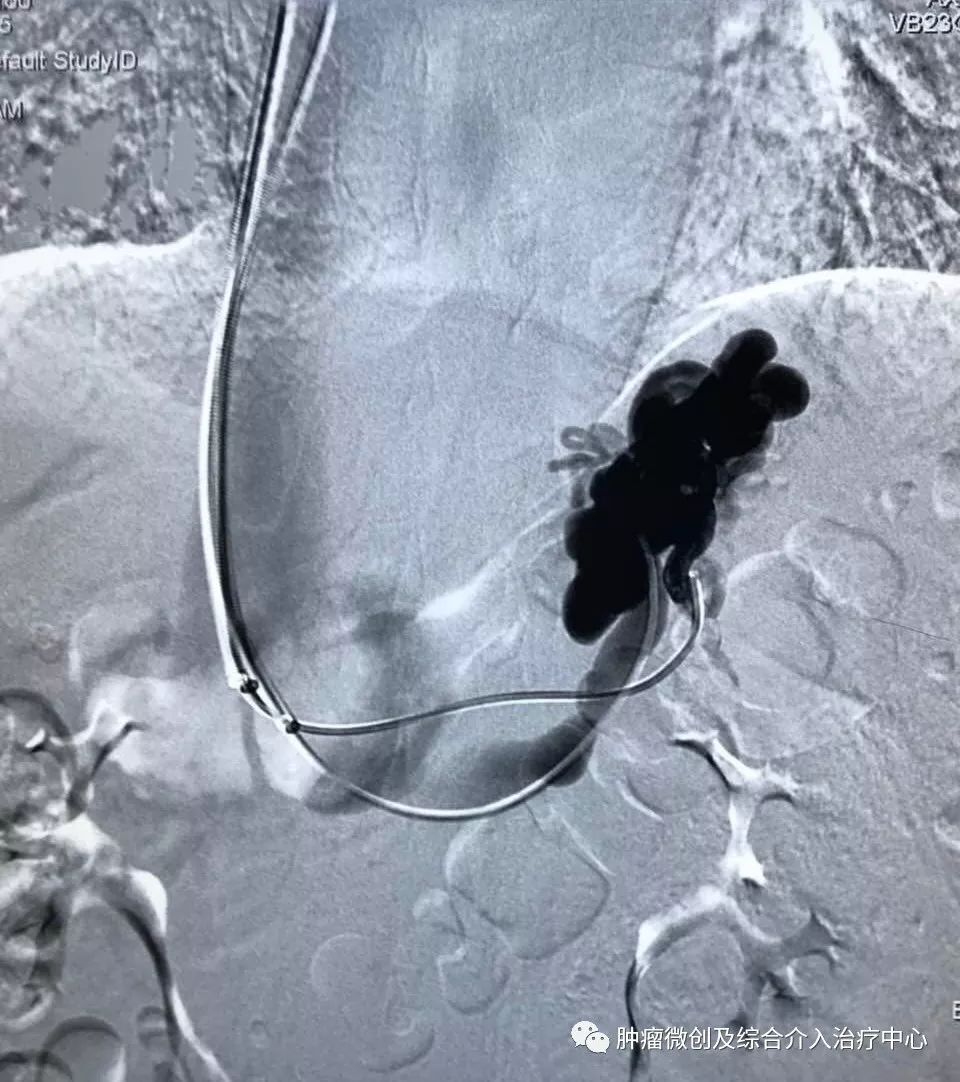

(肝静脉-门静脉穿刺成功,门脉高压,门静脉扩张明显)

(肝静脉-门静脉支架置入搭桥术,分流门脉部分血流,门脉压力降低)